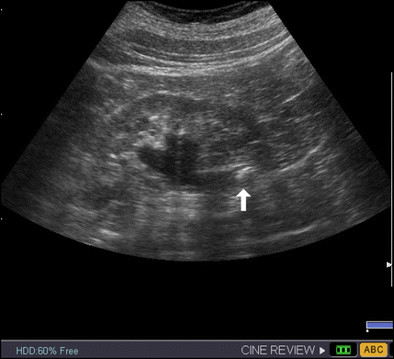

6. kép:

Húgyvezeték kő 1.

Ezen a képen egy követ láthatunk az ureter kezdeti szakaszán (fehér nyíl). Az előtte lévő szakasz valamint a vese medence tágabb.